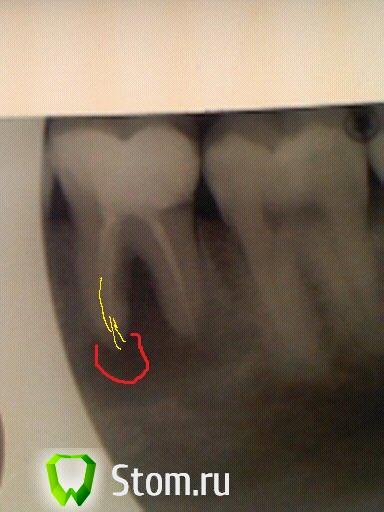

Heineken Опубликовано 16 февраля, 2012 Поделиться Опубликовано 16 февраля, 2012 Каналы прочистили, в дистальном нашли второй. Закачали метапекс, инструмента вроде не было.RE Мне кажется у Вас проблеме больше в медиальном. Попытался отметить на снимке, где вижу её. Ссылка на комментарий